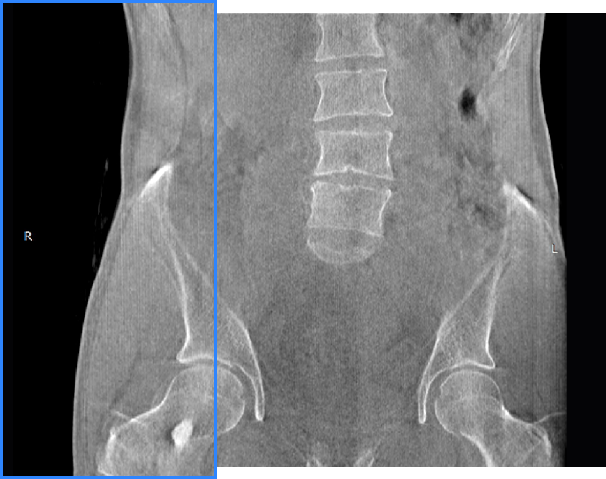

髋关节

填补常规CT/MR空白

助力术前规划和术后评估